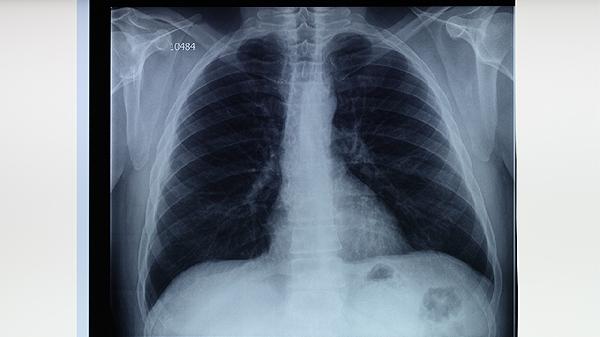

胸部X線能顯示肺結(jié)核特征性病變,如上肺野浸潤影、空洞形成或纖維鈣化灶。典型影像學(xué)表現(xiàn)結(jié)合臨床癥狀可初步診斷,但需注意與肺炎、肺癌等疾病鑒別。對于痰涂片陰性但高度懷疑肺結(jié)核的患者,影像學(xué)檢查具有重要參考價值。